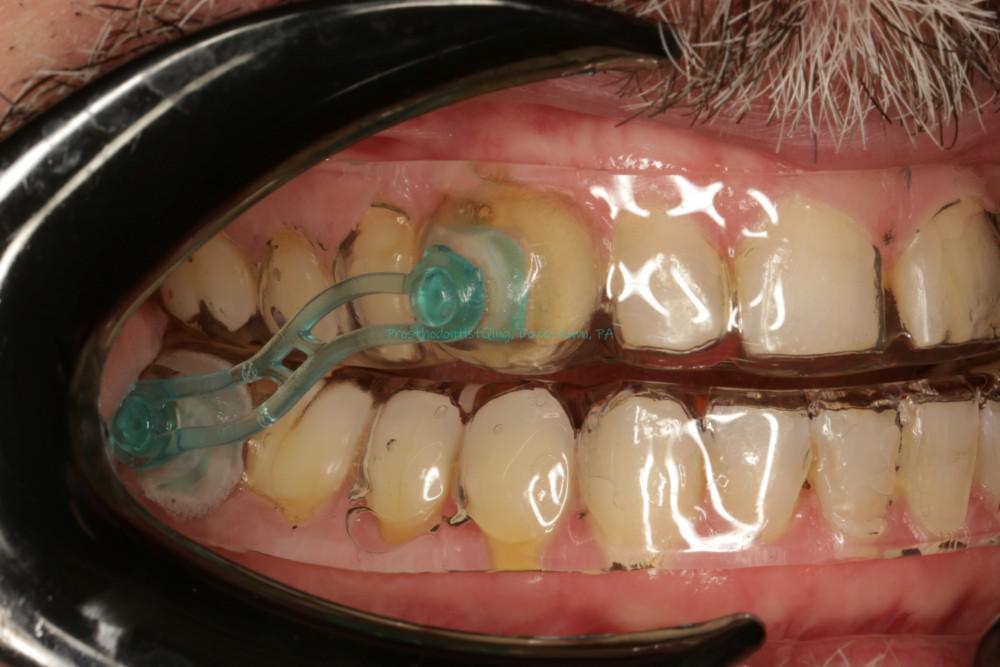

Pictures show the mandible advancing device, which move the lower jaw forward to open the airway during sleep. The main advantage is that 1. effective to treat mild to medium obstructive sleep apnea, 2. no noise compared CPAP machine, 3. small and easy to carry, 4. relatively easier to adapt to, 5. serve as the night guard to protect teeth. Disadvantages included 1. uncertain results in treating severe sleep apnea; 2. Risks of teeth movement, occlusion change and TMD; 3. Requires teeth to anchor the device, so harder for patients with many missing teeth or loose teeth.